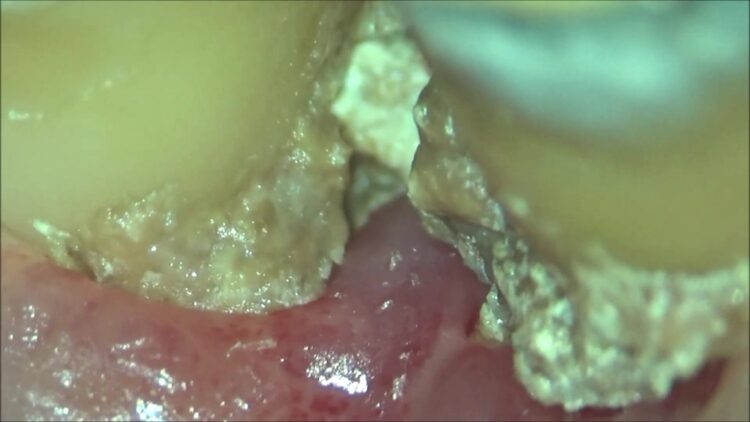

現在の歯の状態は、

腫れは引いても、骨が無いのでエアーをかけただけでグラグラする、

少し触っただけで出血をし、歯石が突起の様に飛び出して歯茎に突き刺さっていました。

歯磨きするのが本当に難しい状態でしたが、ここまで頑張って綺麗にしていただけたおかげで、いよいよ歯石を除去する事ができます。